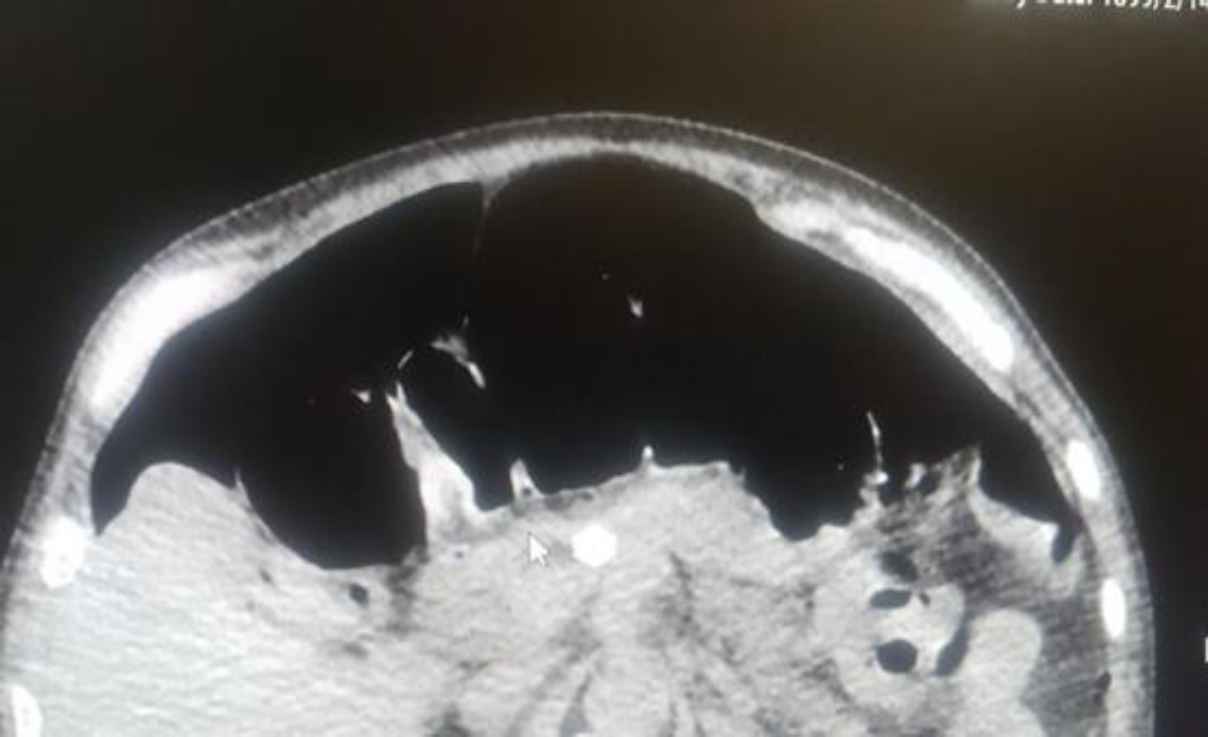

A 60-year-old man was admitted to the intensive care unit (ICU) due to COVID-19 with no past medical history, and infection was confirmed by the COVID-19 PCR test. Four days after admission, the patient complained of abdominal pain and inability to expel gas and excrete feces. The patient’s consciousness decreased the day before the surgical consultation. The surgeon reported tenderness and rebound tenderness during the physical examination. Free air was confirmed by an abdominal CT scan (Figure 5). Blood tests also determined a mild decrease in platelet (130,000/μL) and an increase in Prothrombin time (PT), Partial thromboplastin time (PTT), international normalized ratio (INR), lactate dehydrogenase (LDH)

bill direct, Aspartate aminotransferase (AST), and Alanine aminotransferase (ALT). Due to signs of peritonitis and free air in imaging, the patient underwent emergency surgery. In this regard, a midline laparotomy was performed, and macroscopic observations revealed that a 60-cm-long intestine near the ileocecal valve and entire colon was necrosis (Figure 6). Unfortunately, two days after surgery, the patient died due to respiratory arrest and hypotension.

Fig. 5.Pneumoperitoneum in CT scan